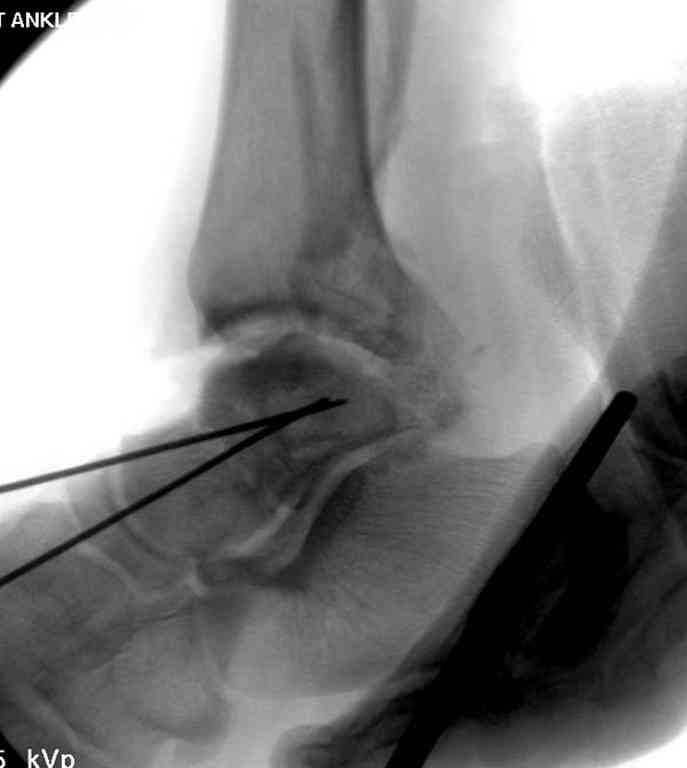

Здесь на фото примеры:

Переломовывих тарана с повреждением медиальной стороны. Через 4 часа после поступления проведена репозиция и фиксация тарана после Irrigation&Debridment. Частичное несращение медиальной лодыжки не беспокоит, вернулся к активному образу жизни. Полная нагрузка разрешена через 11 недель. Финальные снимки через 11 месяцев.

Второй случай прооперирован вчера.

10 дней назад поступил с открытым повреждением медиальной лодыжки и переломо вывихом таранной кости. Ургентно сделана репозиция с наложением наружного фиксатора + Irrigation&Debridment.

Во время репозиции выявили повреждение заднего сухожилия м. тибиалис и задней большеберцовой артерии. Медиальную рану удалось закрыть частично и установлен вакуум.

Дважды провели Irrigation&Debridment с заменой вакуума.

Вчера провели фиксацию.

Из-за многооскольчатости дистальной части малоберцовой, где невозможно было провести фиксацию шурупами, перелом зафиксирован подпирающей пластиной, которая должна служить дополнением отсутствующей дистальной части малоберцовой (lateral cortex substitute).

Для стабильности два шурупа на синдесмоз.

Медиальную рану с приближенными краями продолжаем вакуумировать (KCI). Наружный фиксатор оставлен на пару недель, надеюсь, небольшая рана будет гранулировать и закроется без кожной пластики. Фиксация медиальной ложыжки не планируется.